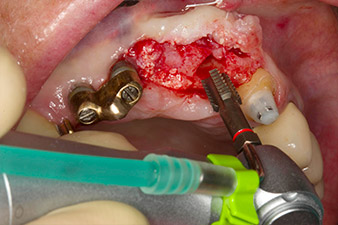

Tapping with the WS-75 L contra-angle handpiece

Fig. 3: Tapping with the WS-75 L contra-angle handpiece at a ratio of 20:1 (programme P4). Implantmed’s high torque, the hexagon chucking system for reliable power transmission and the automatic reversal of the direction of rotation when resistance gets too high prove particularly helpful here.